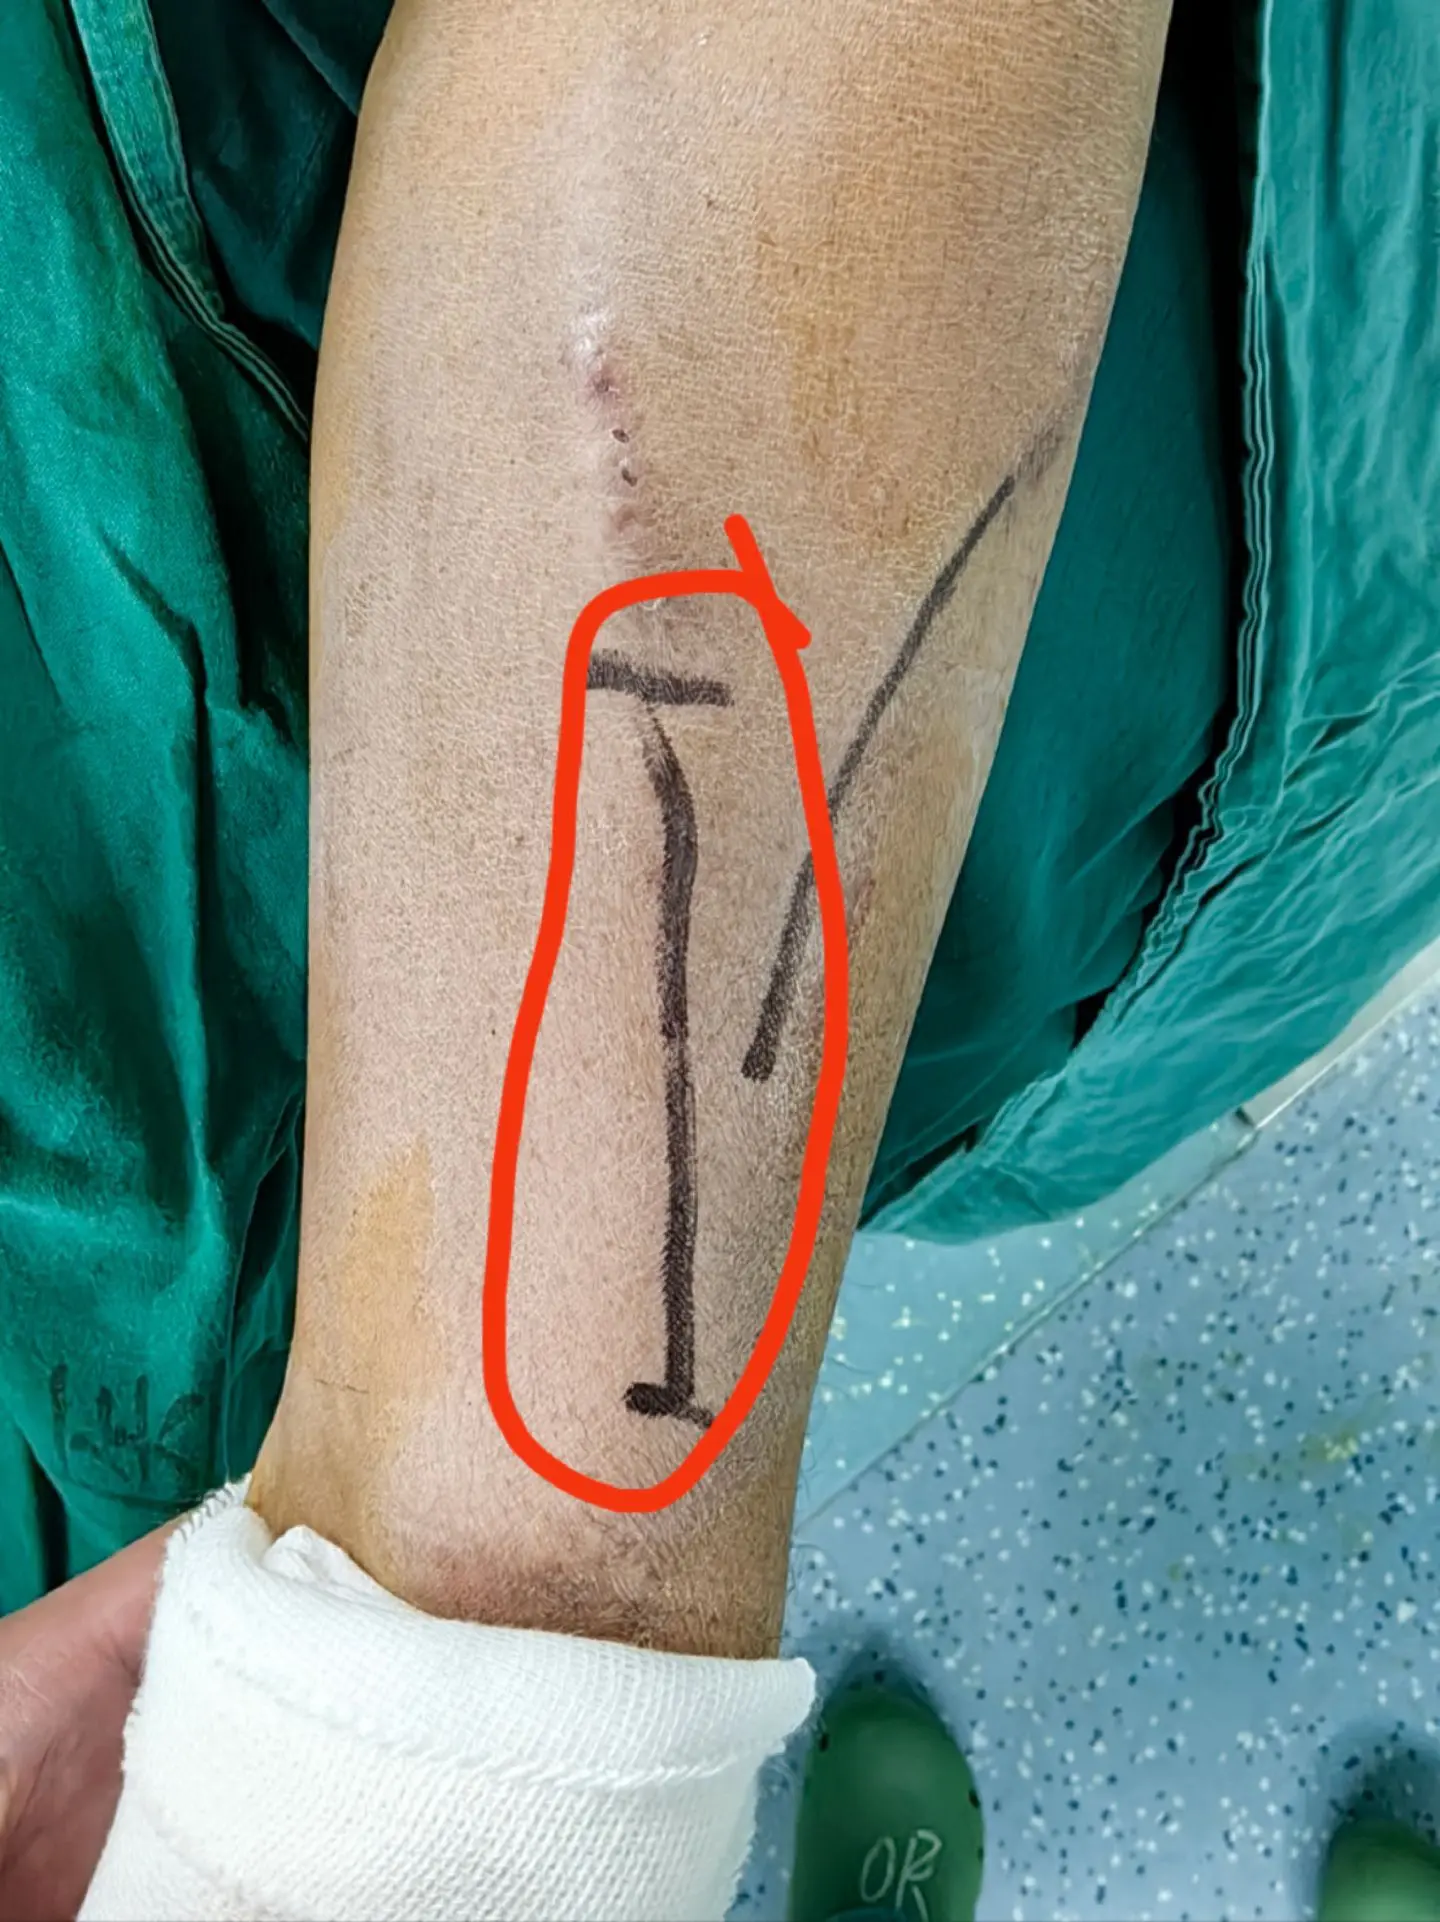

为血透患者维护生命线